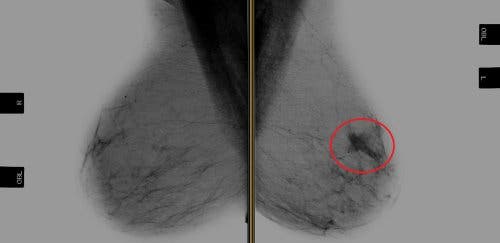

El trastuzumab es la primera terapia dirigida contra un oncogén para pacientes con cáncer de mama HER-2 positivo. Un oncogén es un gen que tienen una gran capacidad de mutación o transformación que induce a la formación de cáncer en un tejido.

Por otra parte, que un cáncer de mama sea HER-2 positivo hace referencia a un tipo neoplasia que tiene sobreexpresados los receptores para esta proteína. Las proteínas HER-2 son receptores de las células de las mamas producidas por el gen HER-2 que en situaciones normales son necesarios. Estas proteínas permiten que las células mamarias se dividan y se reparen por sí solas.

Los cánceres de mama HER-2 positivos representan entre el 20 y el 30 % de los tumores de mama en los seres humanos. Este tipo de cáncer estaba correlacionado con un mal pronóstico, como una supervivencia libre de recidiva y una supervivencia global reducidas.